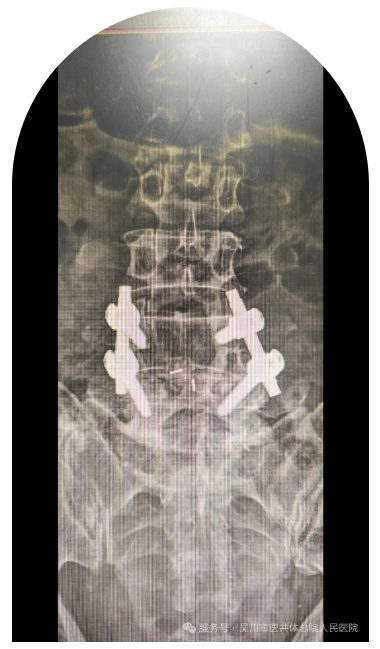

患者刘先生因“高处坠落致全身多处疼痛及腰部、双足跟活动受限3小时”由急诊收入骨外科三区。入院后经过一系列综合检查,诊断为1.腰1、3椎体骨折; 2.胸12椎体下关节突骨折;3.左侧骶椎骨骨折; 4.双侧跟骨骨折 ;5.下颌部、左手掌软组织挫擦伤。

骨外科三区的专家团队经过综合讨论并取得患者及家属的信任后,为患者施行经皮胸12、腰1、腰2、腰5、腰4撑开钉棒复位内固定术和双跟骨骨折切开复位钢板内固定术+植骨术。术程顺利,患者的身体情况恢复良好。